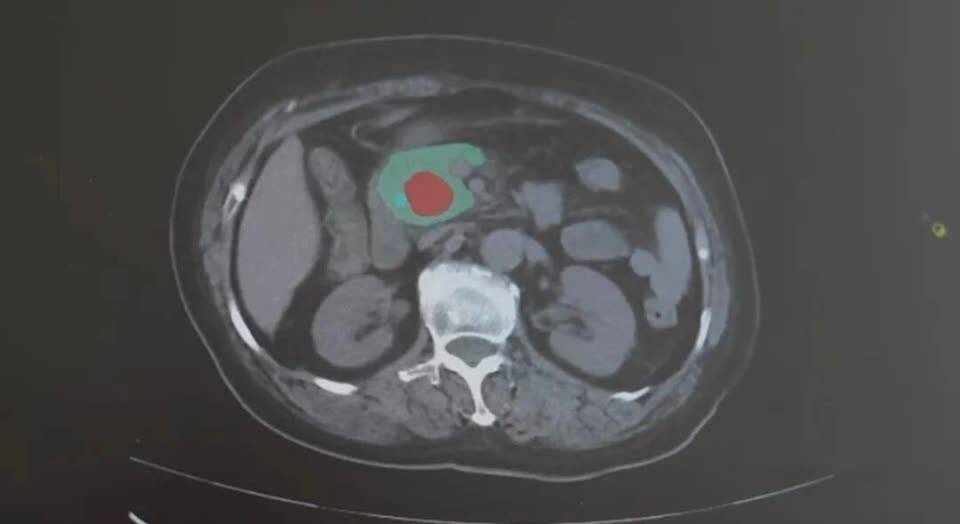

1月3日下午做了一个CT,PANDA预警了,91%的可能性是恶性的。我们AI检查发现他这个胰腺里面它有一个2.5厘米的病灶。然后我们联系到患者,1月12日做的手术,恢复很顺利。

癌的话就是用红色去标志,这个肿瘤大小大概是2.2厘米。PANDA最早的时候能够找到9毫米以下的(肿瘤),我们叫做T0级,差不多是原位癌的级别,非常小一个就能找出来了。